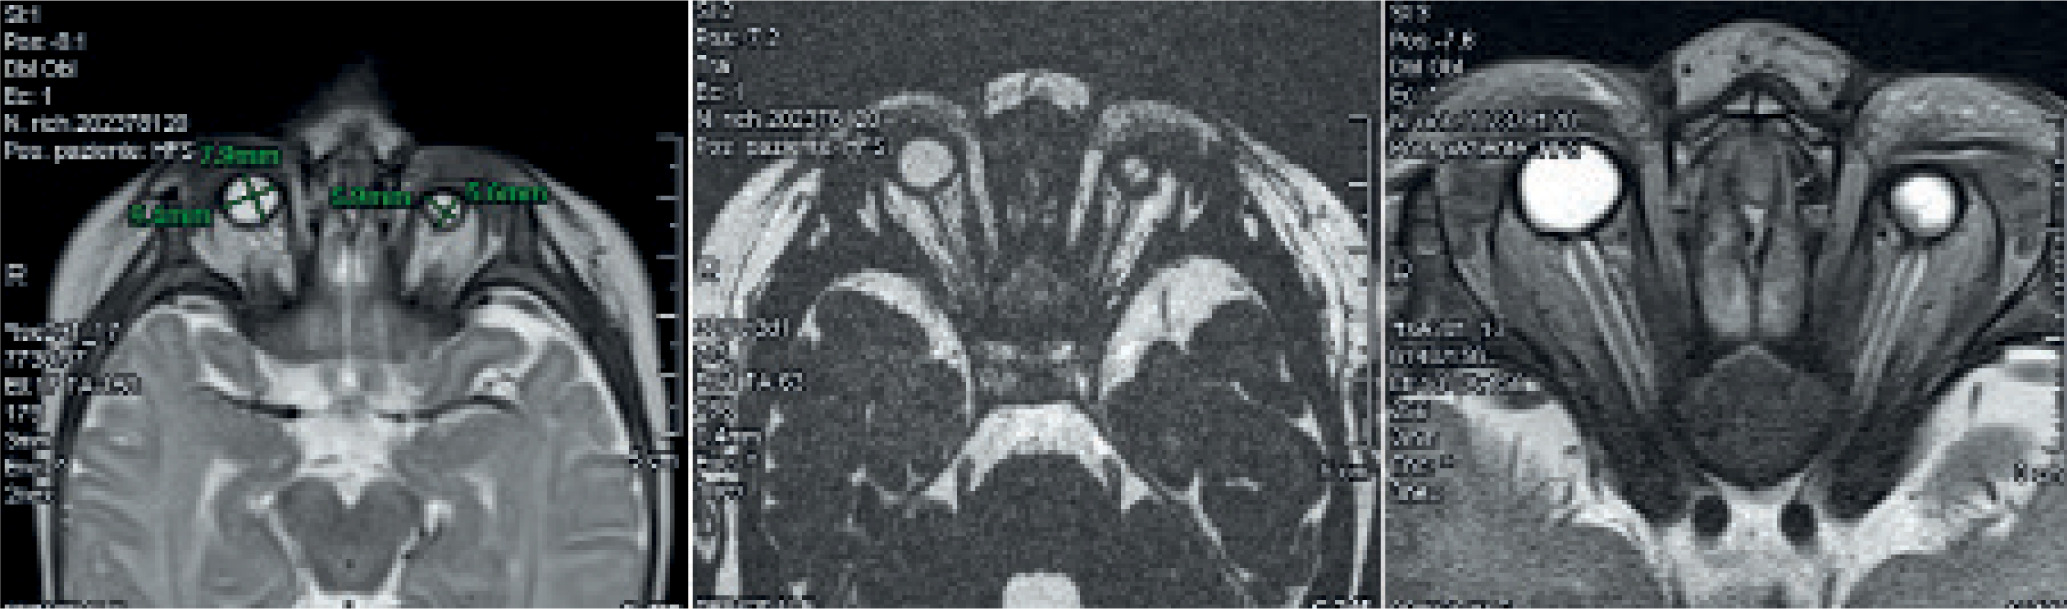

Magnetic resonance imaging (MRI) with contrast was performed when the child was approximately two months old to better visualize the ocular structures and assist in making a definitive diagnosis (Figure 3).

The detailed study of the orbital regions confirmed the presence of bilateral microphthalmia, with a marked reduction in globe size, more pronounced on the left side. The left globe measured approximately 6 × 5.5 mm, while the right measured about 9.5 × 8 mm.

Unfortunately, the optic nerves were thin and not clearly distinguishable bilaterally. The left optic nerve appeared more attenuated than the right. The extraocular muscles, particularly in the posterior region of the left globe, were slightly reduced in thickness and showed a mildly inhomogeneous nodular appearance, though without definitive signs of fat infiltration.

There were no focal or significant signal abnormalities in the supratentorial or infratentorial brain parenchyma. Myelination of the posterior limb of the internal capsule was appropriate for age. No abnormalities in diffusion were observed, and there were no signs of acute ischemia or areas of increased signal intensity. The ventricular system and subarachnoid spaces appeared normal in shape, size, and volume. The midline structures were unremarkable.